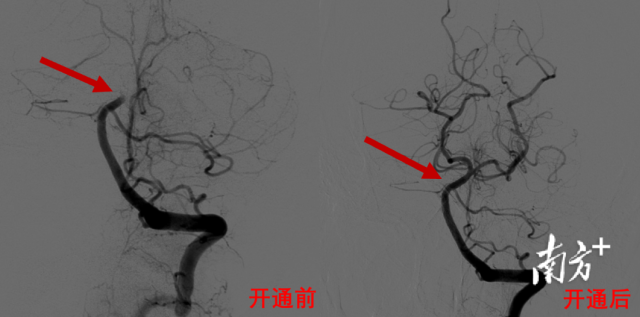

省二医神经医学中心主任兼脑血管病中心主任何旭英、副主任医师卢海克通过脑血管造影,发现唐大哥的脑血管状况非常差,手术难度高,右侧椎动脉先天发育不良,未汇入基底动脉,左侧椎动脉竟然也闭掉了。

“路上不去,就没法做手术,更挽救不了患者的生命。”脑血管病介入团队当机立断,没有路也要开一条路出来,经过努力,开通了闭塞的椎动脉,并置入了支架保障持续的通畅性,再进一步直达基底动脉。

经过紧锣密鼓的手术、熟练干脆的取栓,团队很快取出基底动脉的一大块血栓,患者堵塞的血管重新开通了。一只脚已经踏入鬼门关的唐大哥,被强势拉回!“多亏多学科医护人员无缝衔接、沟通配合,才能在这么短的时间完成手术,与死神赛跑,挽救了病人的生命。”何旭英主任说。